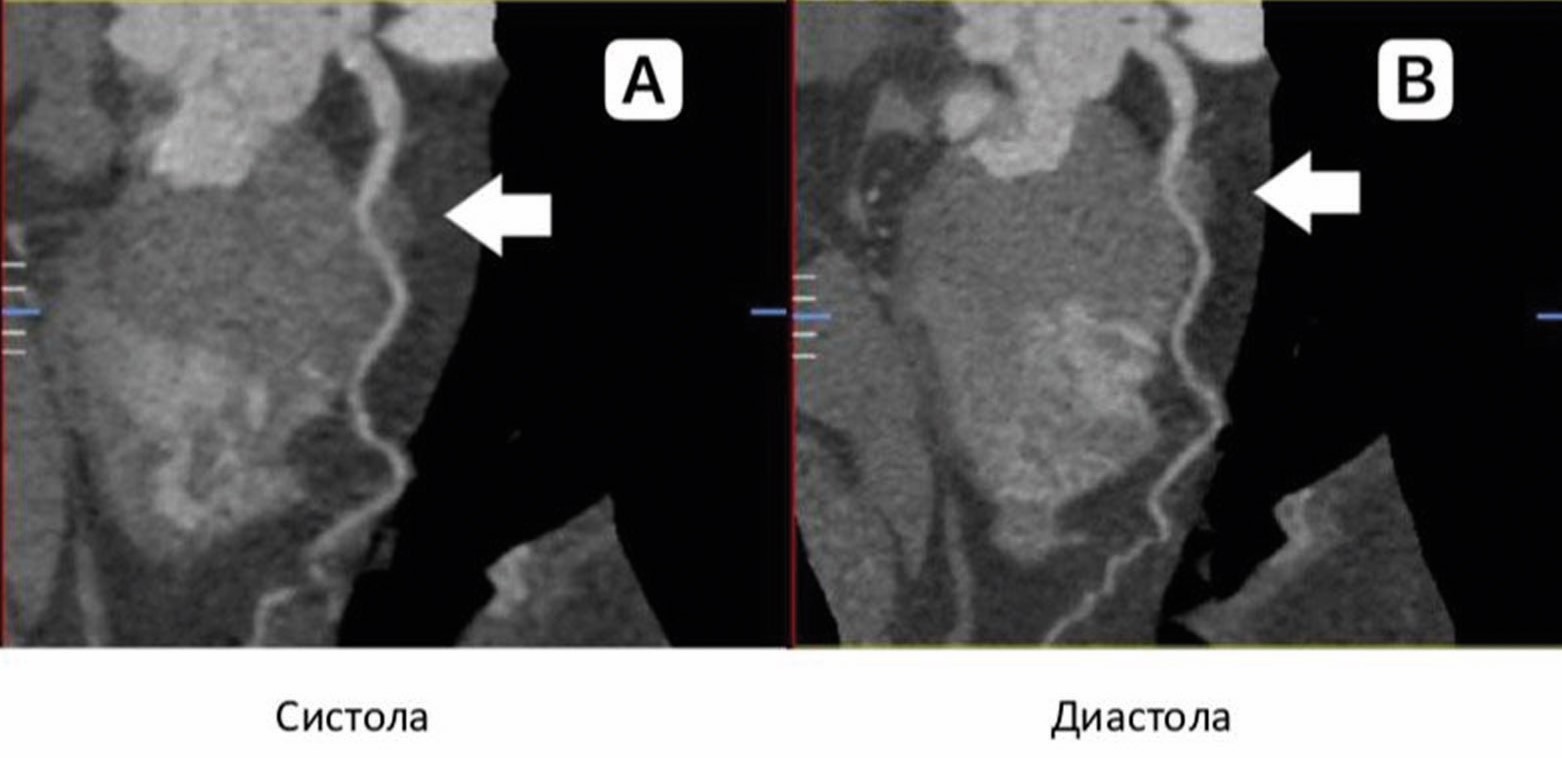

Многие исследователи приходят к заключению, что ММ в среднем встречаются в каждом третьем случае. Наименее чувствительным – от 0,5% [1] до 18% [2] – методом диагностики ММ является селективная коронарная ангиография (КАГ) (рисунок 1).

Рисунок 1. Типичные характеристики ММ при КАГ. На изображении (А) визуализируется фрагмент ММ, подвергающийся компрессии в систолу. В той же артерии во время диастолы (В) сегмент ММ не подвергается компрессии.

Figure 1. Typical characteristics of the myocardial bridge under angiography. Image (A) shows a MB fragment undergoing systole compression. In the same artery, the MB segment is not compressed during diastole (B).

Диагностическим симптомом ММ является «эффект доения» и/или феномен «шаг вниз – шаг вверх», вызванный сокращением мышцы в систолу. Стоит отметить, что КАГ коронарных артерий (КА) является «золотым стандартом», например, при диагностике гемодинамически значимых стенозов венечных артерий или шунтографии. Она имеет некоторые технические ограничения по сравнению с другими новыми методами визуализации, такими как внутрисосудистое ультразвуковое исследование и мультиспиральная компьютерная томографическая коронарная ангиография (КТ-КАГ). Проведение КТ-КАГ позволяет лучше визуализировать ММ – от 26,6% [3] до 73% [4] случаев. Компьютерная томография определяет ММ как фрагмент артерии, который частично или полностью окружен миокардом. Последние разработки, позволяющие выполнять функциональную оценку, дополнительно повышают диагностическую ценность КТ-КАГ для выявления гемодинамически значимых ММ (рисунок 2).